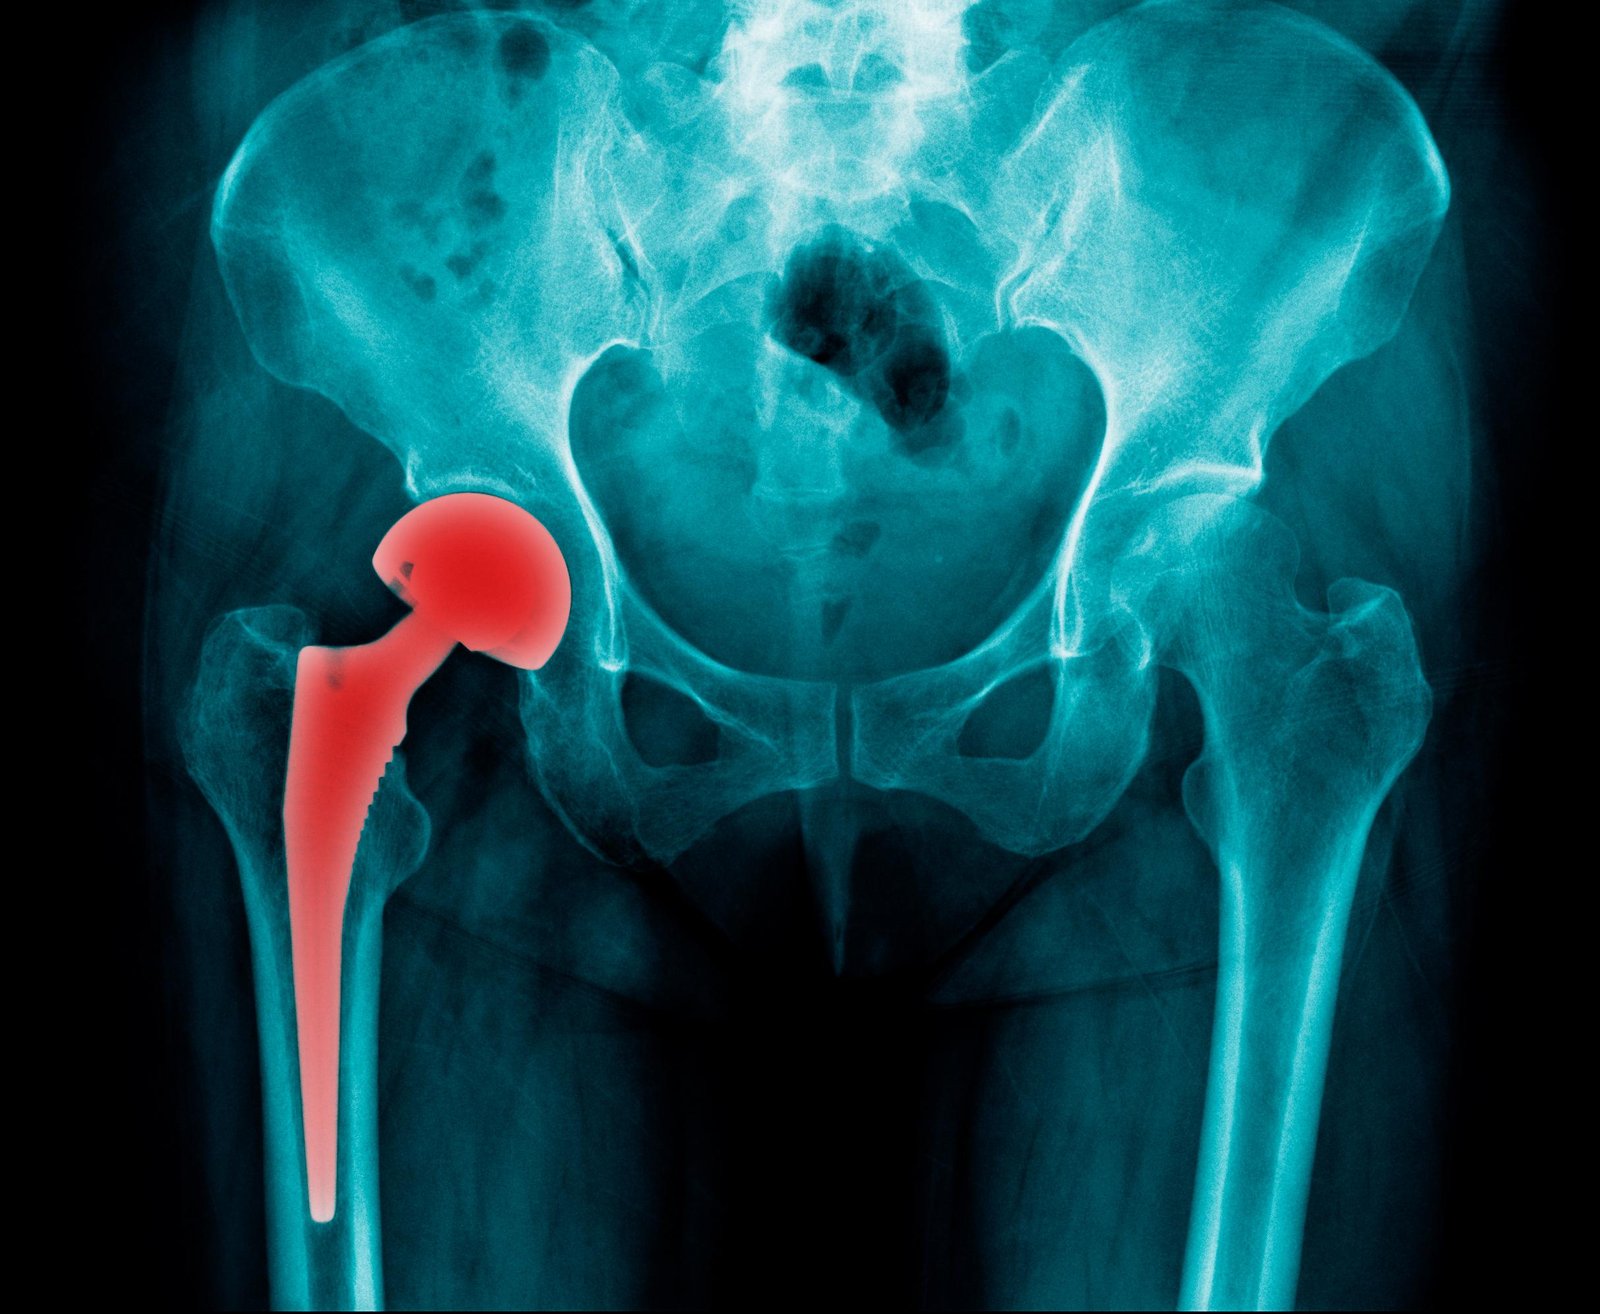

Hip arthoplasty

Hip arthroplasty is the surgical formulation or reformation of hip joint.

2) Total hip arthroplasty: In total hip arthroplasty, the femoral head and neck, ream the femoral canal and insert a metal femoral component (which includes head neck and steam) into the femoral shaft.

[Ref-Lippincott, Adult orthopedic Nursing, P-295]